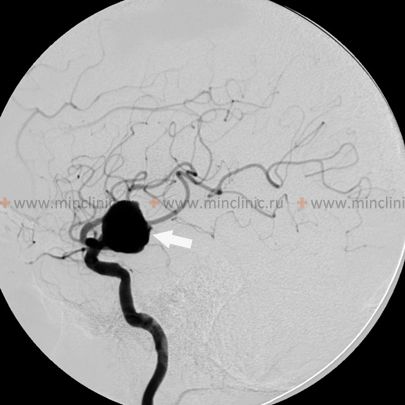

Giant intracranial aneurysms, defined conventionally as those with a maximum diameter greater than or equal to 25 mm, generally occur in the same locations along the cerebral circulation as smaller aneurysms, typically arising at vessel branching points or areas of hemodynamic stress [1, 3]. Common locations where giant cerebral aneurysms are found include the intracranial internal carotid artery (particularly at the origin of the posterior communicating artery, anterior choroidal artery, or the carotid terminus bifurcation), the middle cerebral artery (MCA) bifurcation or trifurcation, and the apex of the basilar artery [1, 3]. While rupture leading to subarachnoid hemorrhage is always a concern with any aneurysm, giant aneurysms often present with neurological symptoms primarily due to their significant mass effect – compression of adjacent cranial nerves, brainstem, or brain parenchyma – rather than solely through rupture [1, 3, 4].

Significant brain edema (swelling) can result from direct compression or potentially from altered hemodynamics related to a giant aneurysm [1]. If severe and progressive, this edema can become irreversible, leading to critical brain compression, increased intracranial pressure, herniation syndromes, and ultimately, patient death [1]. This risk of severe, life-threatening mass effect might be particularly high with certain giant aneurysms, such as those located at the middle cerebral artery bifurcation where they can compress large areas of the temporal or frontal lobes [1]. In situations with acute neurological deterioration due to mass effect from a giant aneurysm, urgent intervention (whether neurosurgical or endovascular) aimed at decompressing the aneurysm or reducing its mass may be the only viable treatment option [1, 5]. However, direct surgical clipping or endovascular treatment (coiling, flow diversion) of giant cerebral aneurysms is often technically challenging due to their size, wide necks, incorporation of vital branch origins, presence of intraluminal thrombus, and calcification of the aneurysm wall [1, 5]. Such complex interventions carry significant risks and can sometimes be complicated by issues like postoperative cerebral edema or incomplete aneurysm occlusion [1, 5].

| Giant Aneurysm (Saccular/Fusiform) | Well-defined vascular outpouching/dilatation ≥25mm. Often arises at bifurcation. May have mass effect (CN palsies, brain compression), headache, +/- rupture (SAH/ICH). | MRI: Often complex signal (flow voids, laminated thrombus). MRA/CTA shows direct connection to parent artery. DSA confirms diagnosis, details neck/flow. |